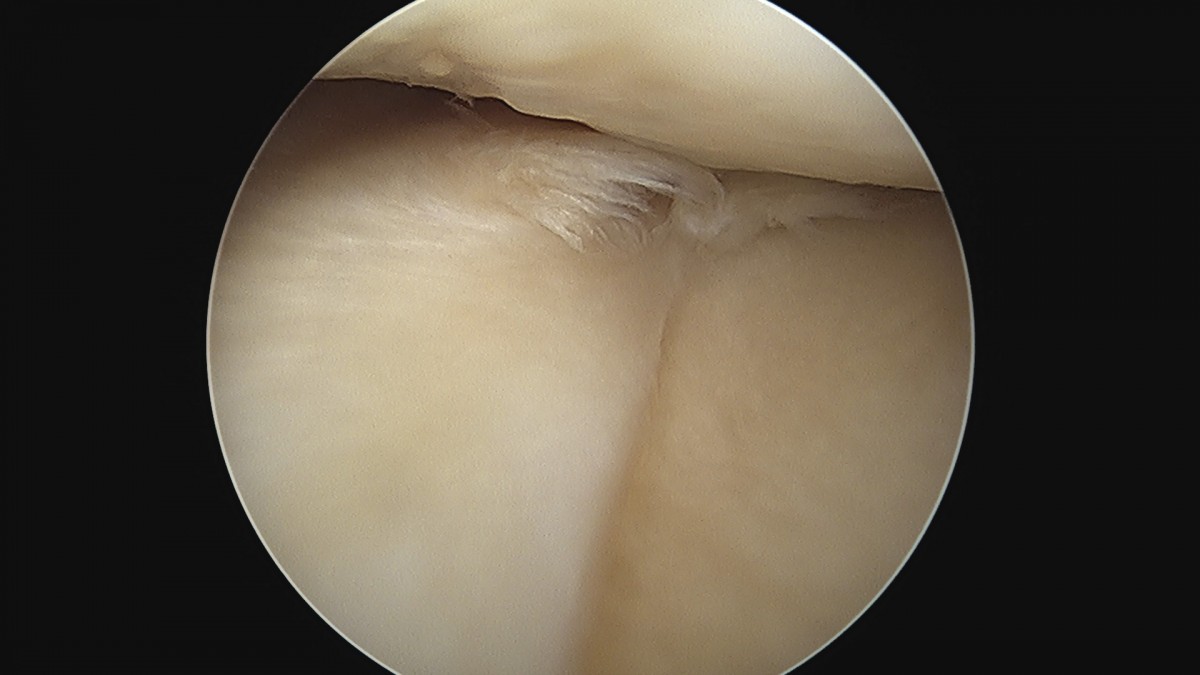

이재상원장님 무릎 반월상 연골판 절제술 안경O 환자

dae765e4d9ac96aee867c9d6292d8784_1758005874_0351.jpg